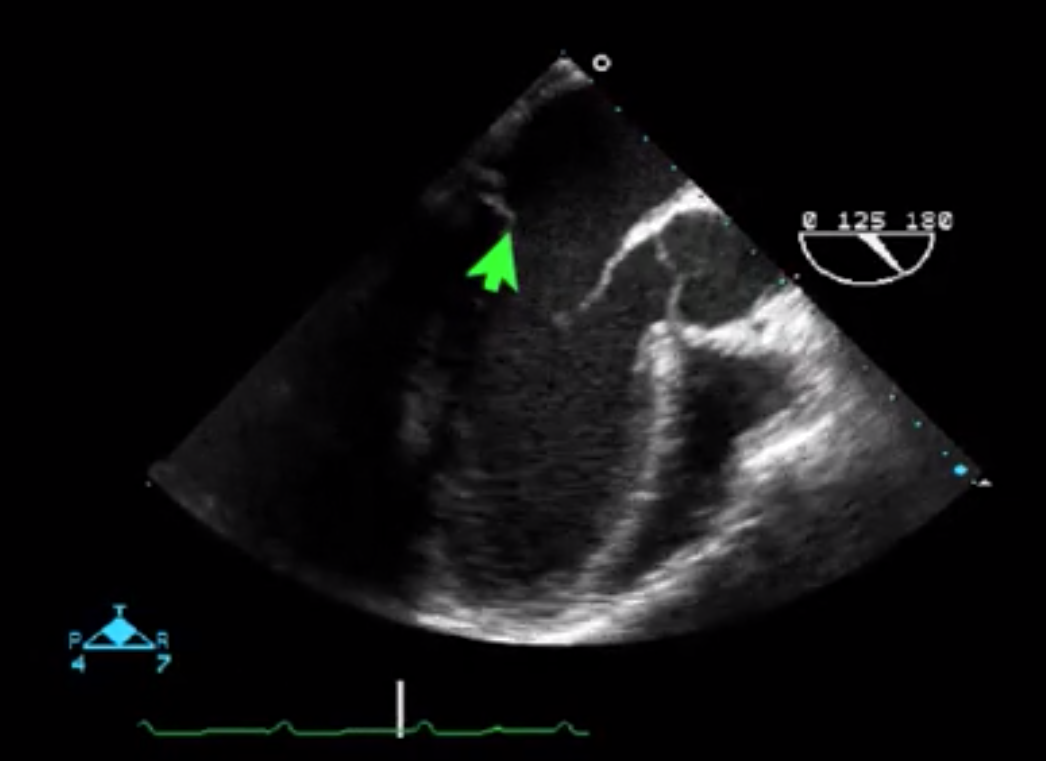

What scallops of the mitral valve are seen in the ME LAX view?

A2 (other unlabeled) and P2 (green arrow)